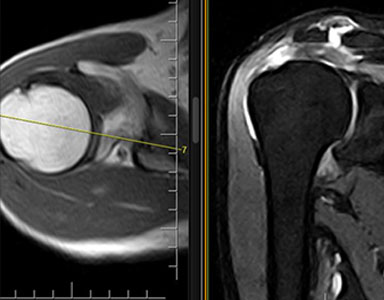

Grazie alle diverse pesature di immagine che possono essere ottenute tramite una scansione RM, si apprezzano, per esempio, a livello lombare ernie/protusioni discali, schiacciamenti vertebrali, crolli, o sofferenze dell’osso intraspongioso; a livello invece osteoarticolare si riesce ad evidenziare con grande precisione i legamenti e i tessuti muscolari che compongono l’articolazione oggetto di studio e quindi, le eventuali patologie correlate a queste, come ad esempio artrosi, lesioni legamentose e muscolari, osteocondropatie.

risonanza magnetica alla spalla